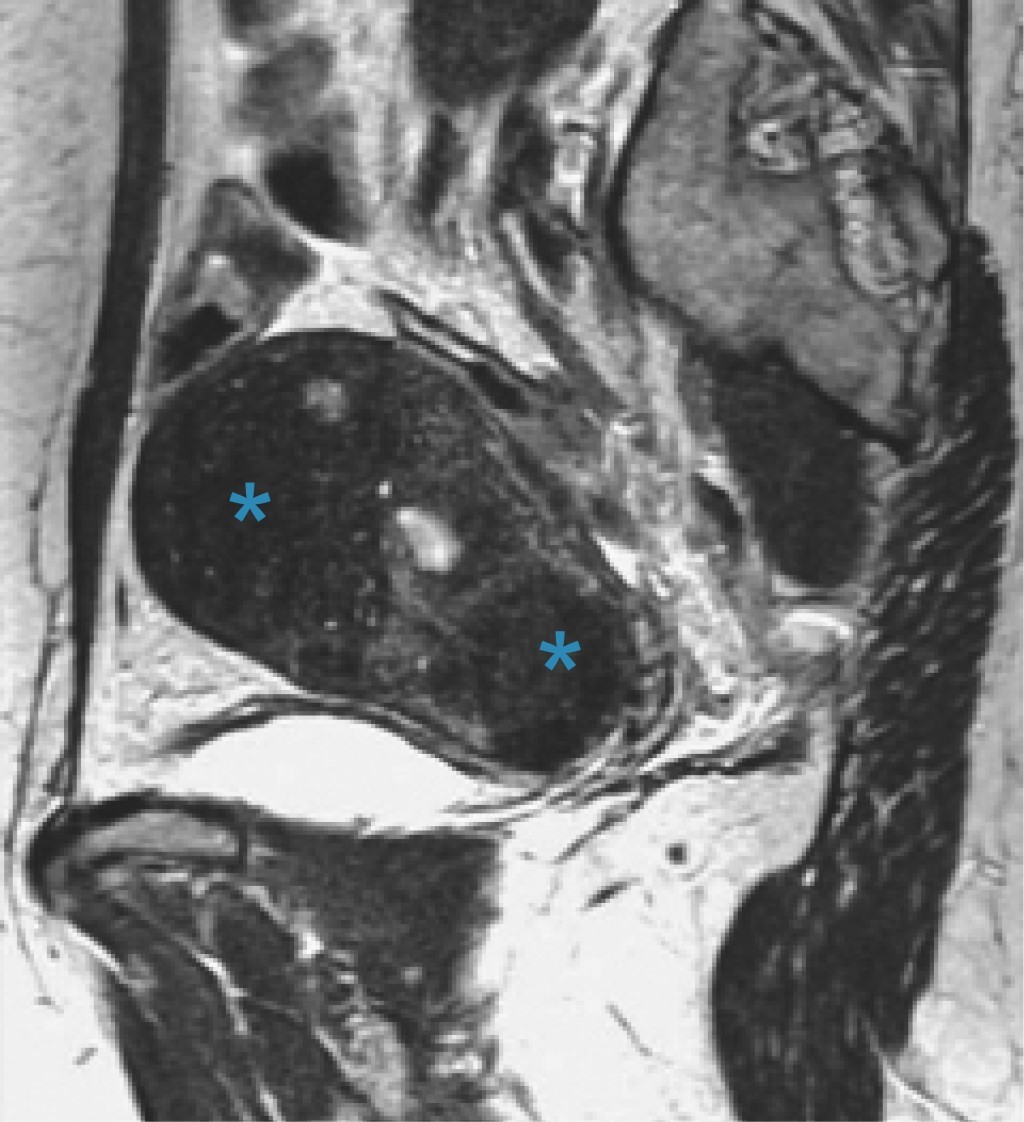

Adicionalmente, los hallazgos por resonancia magnética pueden ser clasificados como signos directos o indirectos. Dentro de los directos se encuentran los microquistes, siendo éstos el principal signo de adenomiosis identificable por resonancia magnética, los cuales tienen un tamaño de entre 2-7 mm, con una media de 3 mm y se encuentran dentro del miometrio (Figura 3),10 además de que se hallan principalmente en la zona de unión y raramente en el miometrio; son hipointensas en T1 e hiperintensas en T2, e identificables de mejor manera al final del periodo menstrual con cavidad quística.11 Los adenomiomas que se encuentran como una consolidación focal de las glándulas adenomióticas dentro del miometrio se manifiestan como una masa de paredes bien delimitadas en la zona de unión, por lo que el principal diagnóstico diferencial es el leiomioma uterino, ya que ambas presentan el mismo grado de intensidad, con la única diferencia que la vascularidad de los adenomiomas presenta más angiogénesis (Figura 4).12

Figura 4